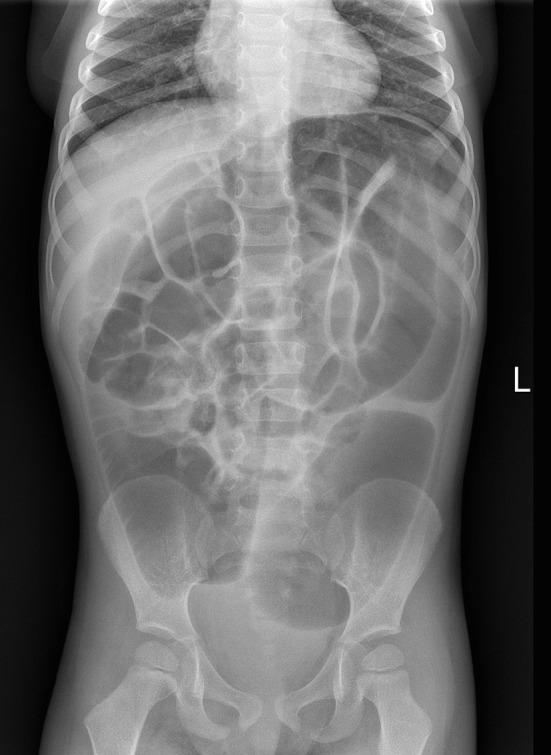

The presentation of eosinophilic myenteric ganglionitis (EMG) can be similar to that of Hirschsprung's disease (HD). In a limited number of cases of pediatric patients, the diagnosis of both EMG and HD are reported. A case of pseudo-obstruction in EMG occurring in a child with HD diagnosis is discussed with literature review. A boy aged 2 years and 6 months presented with intractable constipation and abdominal distension. Histological HD diagnosis was carried out and transanal Soave pullthrough was performed. At the age of 3 years and 2 months, an infectious enterocolitis occurred. One month later, he presented with constipation, marked abdominal distension and melena. Full thickness colonic biopsies revealed eosinophilic myenteric ganglionitis. Specific IgE tests were positive for several foods. Dietary exclusion was adopted with resolution of clinical symptoms and histologic remission. EMD may occur in patients with HD. At the onset, EMD may be associated with functional intestinal obstruction. The use of an elimination diet proved effective for the relief of symptoms. Long term follow-up is mandatory to define the timing of the reintroduction of foods.

嗜酸性肌间神经节炎(EMG)的表现可能与先天性巨结肠(HD)相似。在少数儿科患者病例中,有EMG和HD均被诊断出来的报道。本文结合文献回顾,讨论了1例诊断为HD的儿童发生EMG所致假性肠梗阻的病例。一名2岁6个月大的男孩出现顽固性便秘和腹胀。进行了HD的组织学诊断,并实施了经肛门Soave拖出术。3岁2个月时,发生了感染性小肠结肠炎。1个月后,他出现便秘、明显腹胀和黑便。全层结肠活检显示嗜酸性肌间神经节炎。多种食物的特异性IgE检测呈阳性。采用饮食排除法后临床症状缓解,组织学病变减轻。EMD可能发生在HD患者中。发病时,EMD可能与功能性肠梗阻有关。采用排除饮食法被证明对缓解症状有效。必须进行长期随访以确定重新引入食物的时机。